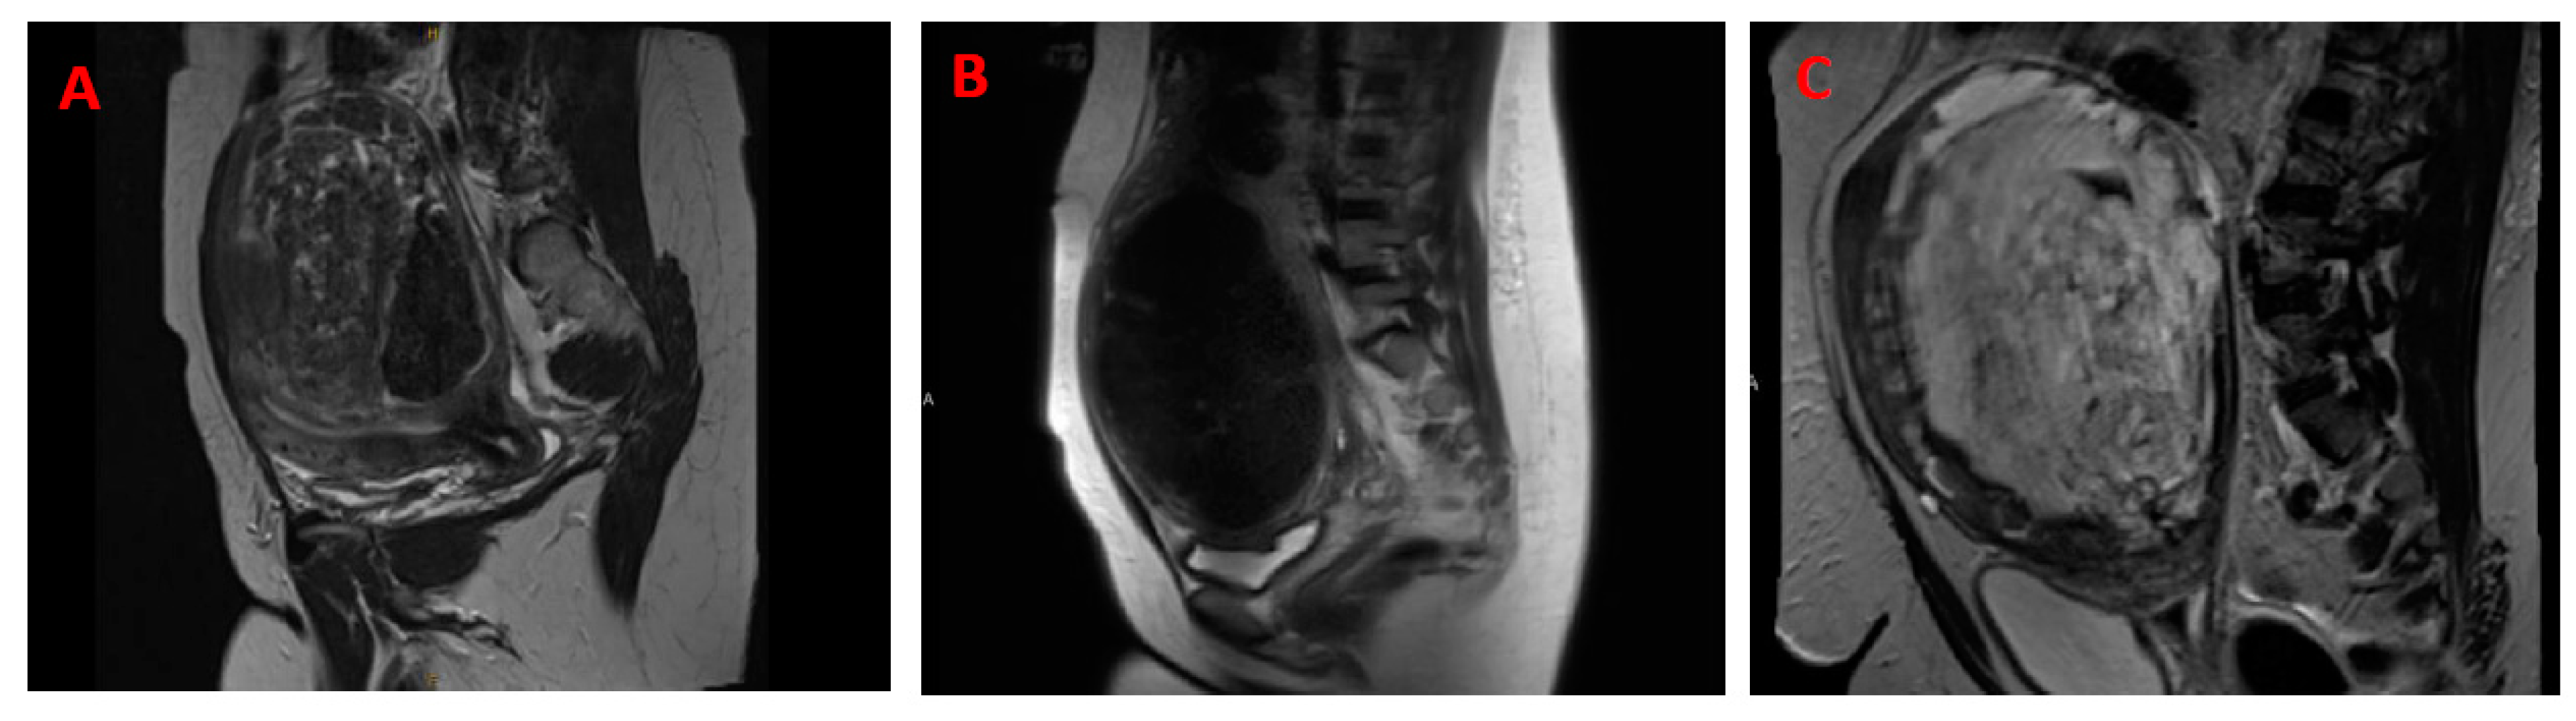

2.2.1. Clinicopathologic Features

6.1. Clinical Diagnosis between Malignant Uterine Leiomyosarcoma and Benign Leiomyoma

6.1.2. Advanced Imaging—Artificial Intelligence and Machine Learning